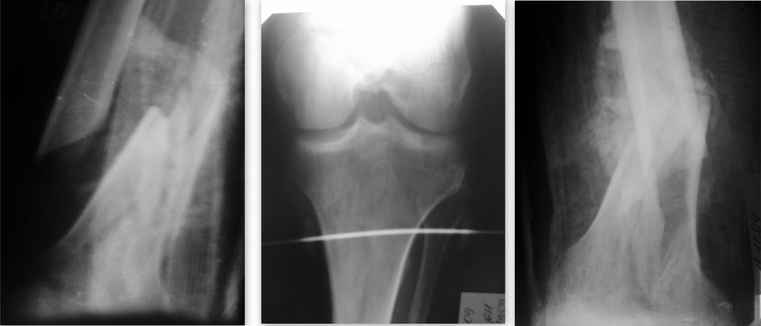

У б-го Тяжелая сочетанная травма от 25.09.09 Ушиб г\мозга. З\оскольчатый внутрисуставной

перелом л\бедра в н\3. О\оскольчатый внутрисуставной перелом п\бедра в н\3. Медиальный

перелом шейки п\бедра. Перелом лонной и седалищной костей справа.

Кахексичен, в жизни алкоголизируется.

В данный момент ЧМТ невелирована до энцэфалопатии смешанного генеза.

Больной доступен продуктивному контакту. Пролежни разрешились. Рана открытого перелома

п\бедра зажила 1-м натяжением. Анализы нормализовались. Правая н\конечность сейчас в

укороченной гипсовой (циркулярной) повязке. На следующей неделе собираюсь синтезировать

левое бедро опорной мыщелковой пластиной с УС. Уважаемые коллеги! Предоставляю данный

случай на обсуждение. С уважением А.М.